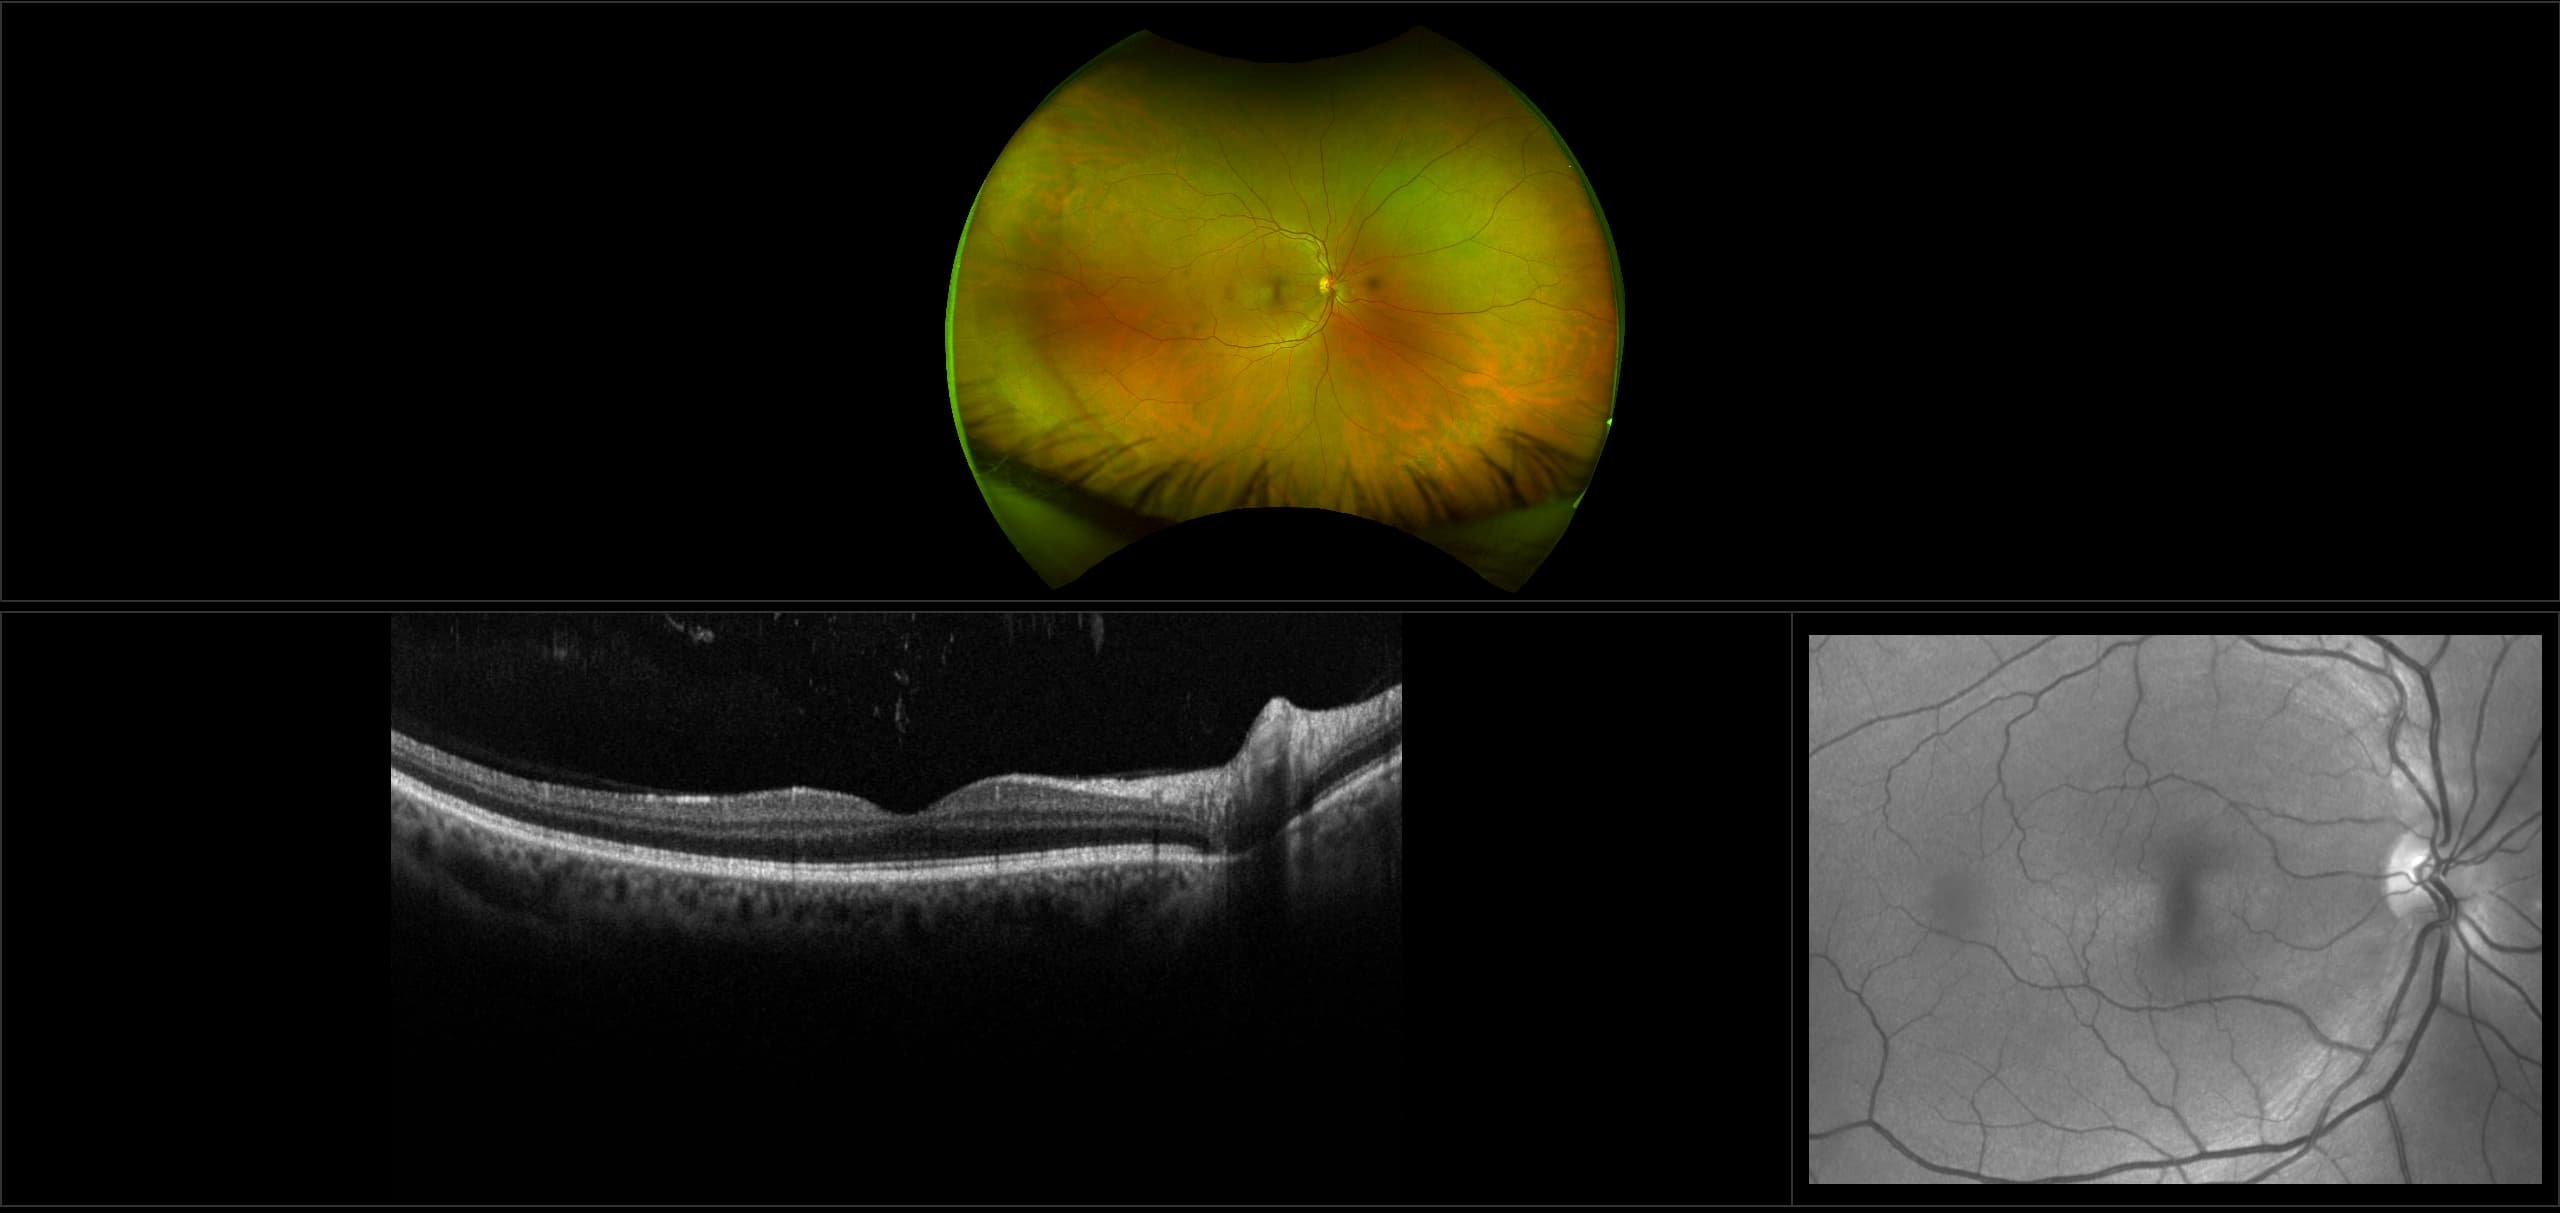

This material is designed as a searchable reference resource to support clinical decision-making. The information contained here should be used as general guidance when viewing optomap and OCT images from Optos devices. The differential diagnosis should be made under the direction of the responsible physician. These images were taken on the latest ultra-widefield optomap devices.

optomap Recognizing Pathology is searchable by pathology and/or optomap image modality. You may search by multiples of each selection. Each individual case is represented by the accompanying thumbnail image. Most cases include several different optomap image modalities. To view a full description of the case, please click on the thumbnail. Each image in the case will be made available through our OptosAdvance software which provides multi-dimensional visualization of digital images to aid in the analysis of anatomy and pathology. Support and pathology definitions can be found by selecting one of the buttons, above. Should you have questions, please complete the form below.